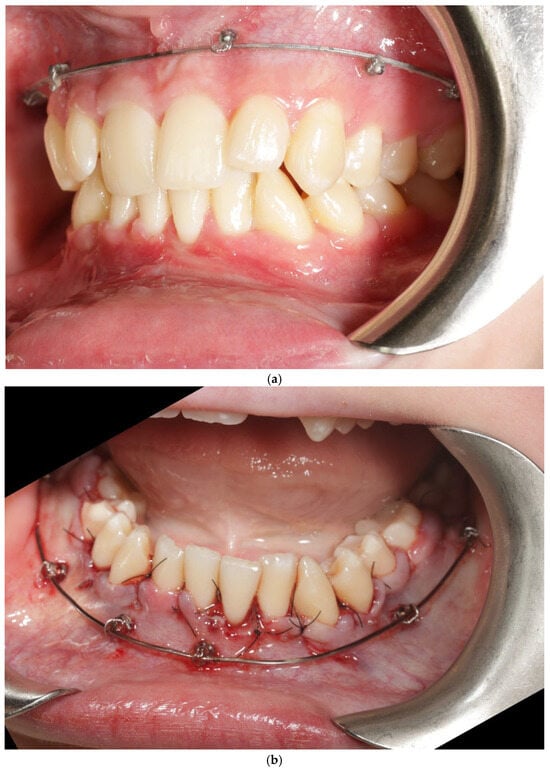

Bone Protection System (BPS). The Bone Protection System (BPS) is a chairside orthodontic adjunct designed to stabilize the vestibular segment during alignment and expansion (Figure 2a,b). Its purpose is to reduce non-physiologic buccal tipping moments and to guide a more axial trajectory of root movement. BPS does not apply active force; instead, it modifies the moment–force environment generated by the archwire–bracket complex by limiting uncontrolled buccal displacement of the crowns. The device is attached passively to the vestibular brackets and remains in place throughout the expansion/alignment phase. Full technical construction details are protected by a filed patent application; therefore, only clinical handling and rationale are described. The system was applied in the first months of orthodontic treatment during leveling and expansion in conjunction with the regional acceleratory phenomenon (RAP). A modified corticotomy was performed, followed by placement of orthodontic mini-implants at seven sites in the buccal segment of the maxilla. An expanded orthodontic stainless-steel archwire was engaged with the mini-implants to deliver the planned expansion mechanics and force vectors. Descriptions of biological responses to these mechanics are beyond the scope of this case report and are addressed in the Discussion. Detailed FEM analyses are reported in a separate bioengineering manuscript under review; therefore no FEM datasets or numerical outputs are reproduced in this case report.

Figure 2.

Patient 1 with Bone Protection System in both arches (a,b).

A CBCT scan was obtained immediately after removal of BPS to verify cortical continuity.

However, metal scatters from brackets and archwire, and the fact that the scan captured only the early remodeling phase, made thin buccal cortices partially invisible due to lack of mineralization. As CBCT detects only mineralized tissue, quantitative assessment was not performed. A full post-treatment CBCT will be obtained after orthodontic finishing, when newly formed bone becomes radiographically detectable [34,35,36,37]. CBCT imaging was performed using a standard dental CBCT unit with a limited field of view and high-resolution settings appropriate for alveolar bone assessment. Given the presence of orthodontic appliances, metal-related artifacts were anticipated. To mitigate their impact, image interpretation was restricted to regions where the buccal cortical plate was clearly visible and not obscured by scatter, and no quantitative measurements were attempted. All CBCT findings in this report are therefore qualitative and were interpreted conservatively, within the limits of scan interpretability.

A CBCT scan obtained immediately after removal of BPS for qualitative assessment of the buccal cortical outline but was affected by metal-related scatter from brackets and archwire. Because the scan captured only the early remodeling phase, buccal cortical visibility was insufficient for reliable quantification, and no numerical CBCT analysis was performed at this stage. A full post-treatment CBCT will be obtained after orthodontic finishing to allow adequate mineralization of newly formed bone.